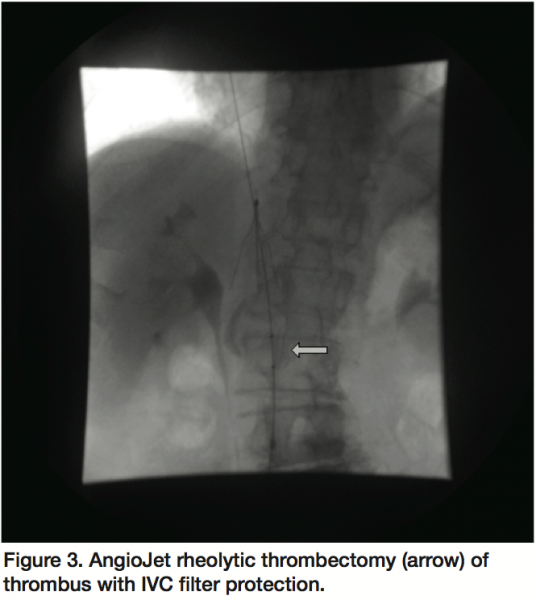

Preceding IVC filter placement, a venogram showed a large filling defect, consistent with a large thrombus, primarily adherent to the medial aspect of the IVC at the origin of the left renal vein (Figure 1). The superior portion of the thrombus had a mobile appearance which was concerning for impending rupture and embolization. A retrievable IVC filter (Celect, Cook Medical, Bloomington, Indiana) was successfully placed between the thrombus and the IVC-right atrial junction (Figure 2). Subsequent to IVC filter deployment, rheolytic thrombectomy (AngioJet, Medrad, Inc., Minneapolis, Minnesota) was performed with 5 consecutive passes within the IVC with significant reduction of thrombotic burden (Figure 3). Final venogram showed a very small residual adherent thrombus without evidence of a mobile component (Figure 4). The patient eventually underwent colonoscopy, which divulged stage 1 colon cancer involving the cecum and consequently, underwent successful partial colectomy with an uncomplicated recovery.